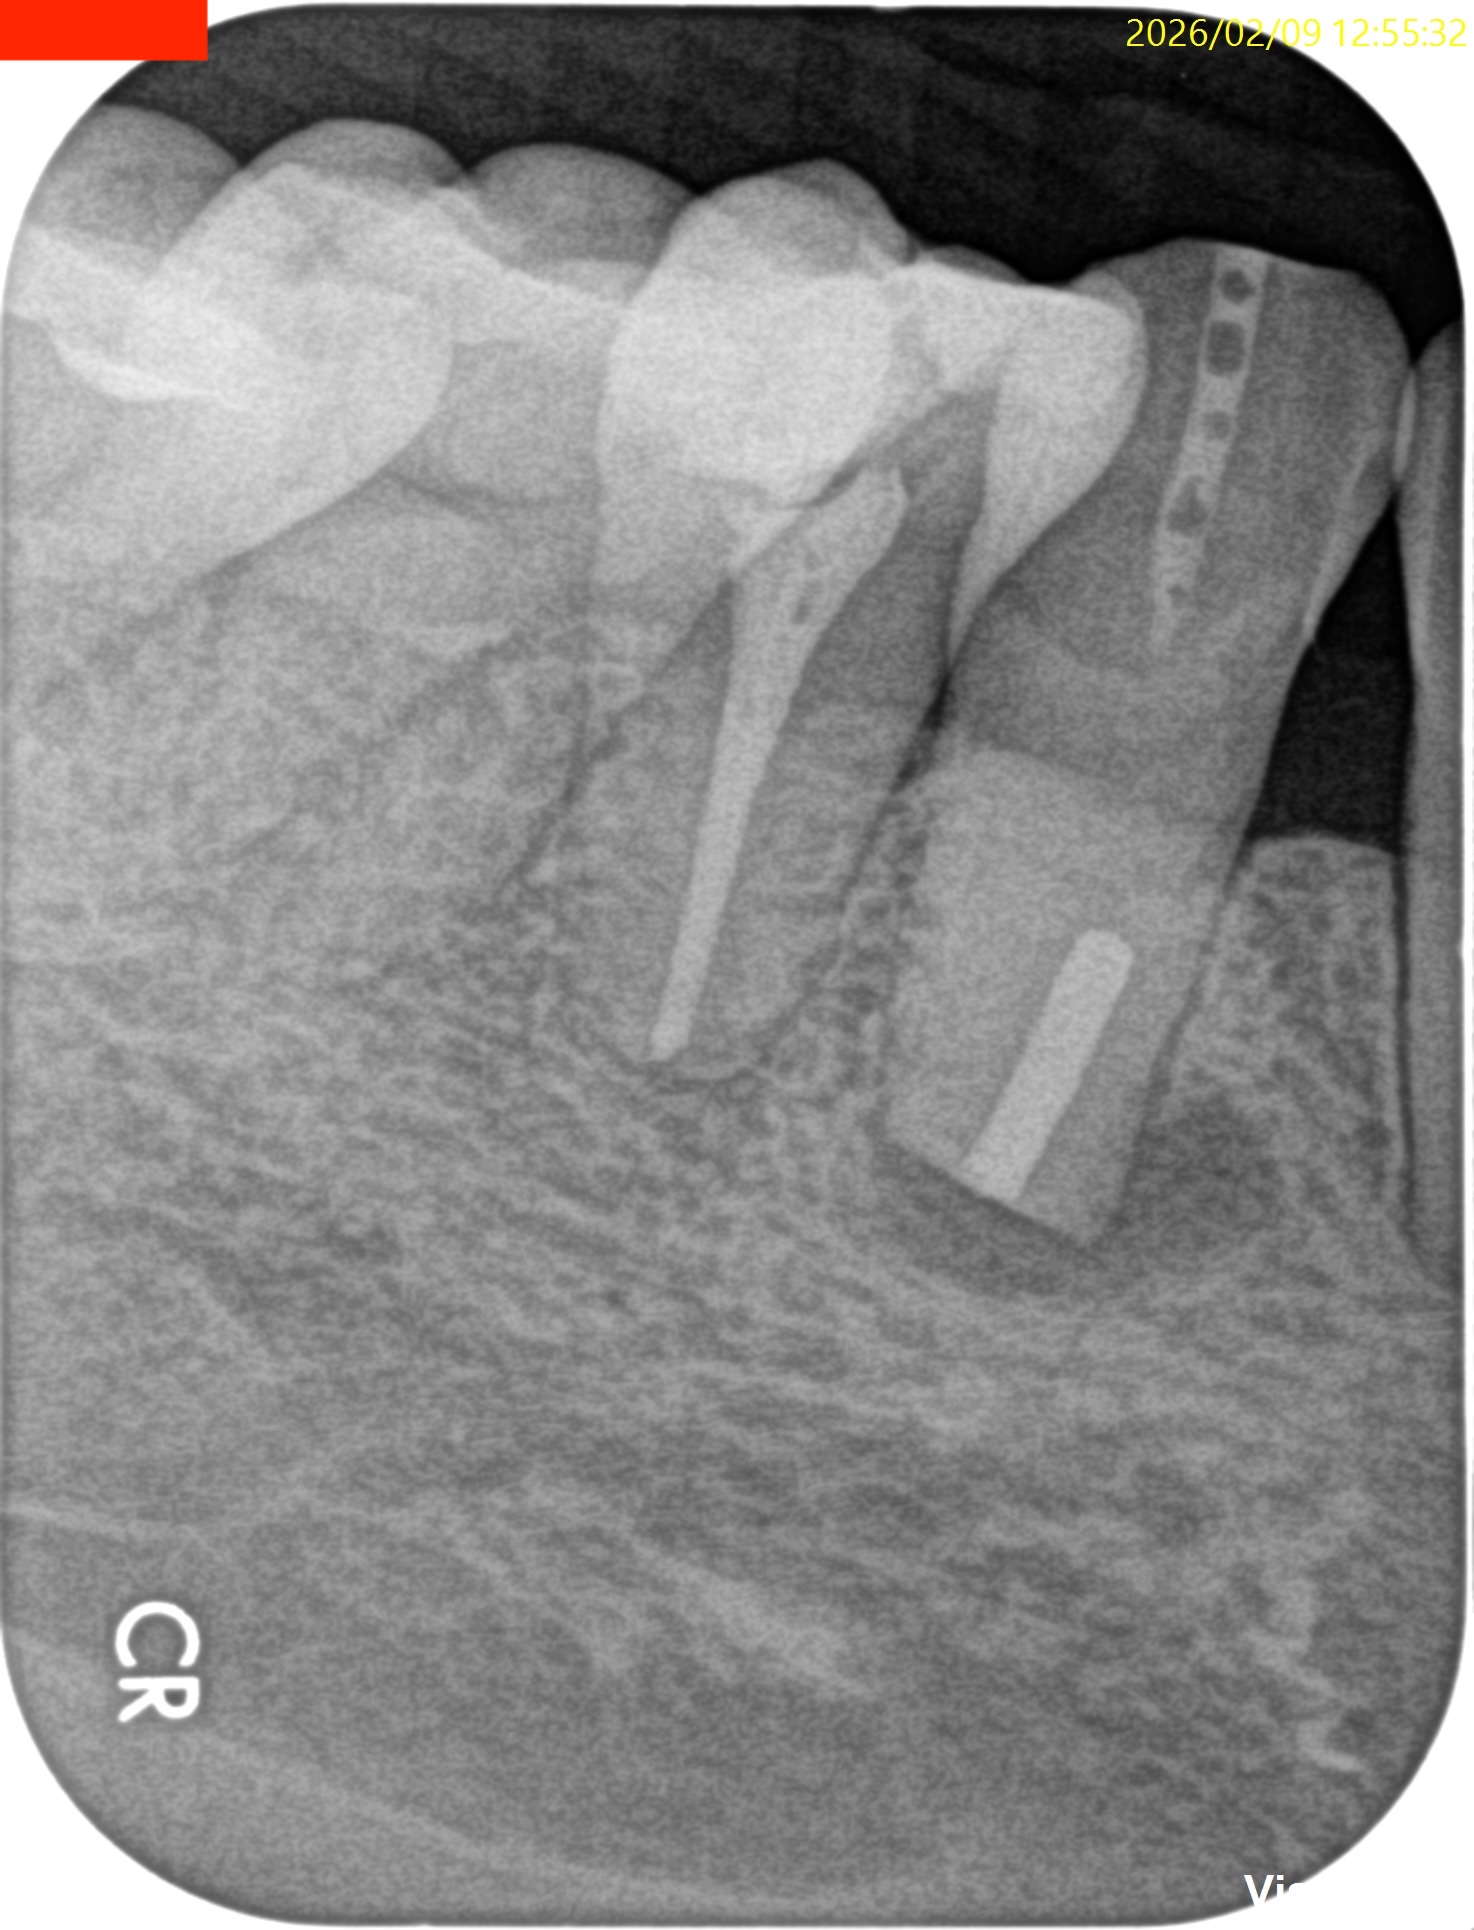

#27 Intentional Replantation(2026.2.9)

犬歯の抜歯は根尖病変があるものの脱臼作業なしでは成り立たないだろう、ということがこのケースからもわかる。

この後、抜歯窩を精査し口腔外作業へ移行する。

破折はない。

根尖部を3mm切断した。

逆根管形成・逆根管充填した。

PAを撮影した。

問題はないだろう。

抜歯窩を生食で洗浄し、再植した。

術後にPA, CBCTを撮影した。

次回は1ヶ月後である。